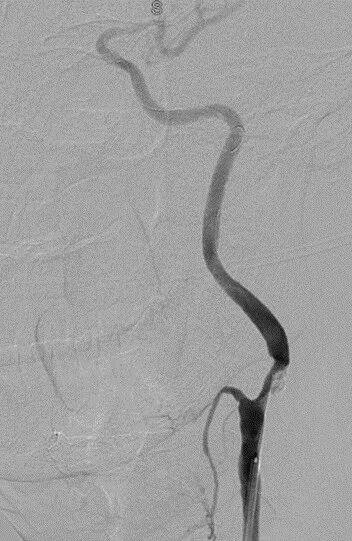

左侧颈内动脉起始段重度狭窄。

波科支架怎么样径技-弓上病例大赏|第205期·放疗后症状性颈动脉狭窄支架置入治疗一例_https://www.jmylbn.com_新闻资讯_第12张

波科支架怎么样径技-弓上病例大赏|第205期·放疗后症状性颈动脉狭窄支架置入治疗一例_https://www.jmylbn.com_新闻资讯_第13张

波科支架怎么样径技-弓上病例大赏|第205期·放疗后症状性颈动脉狭窄支架置入治疗一例_https://www.jmylbn.com_新闻资讯_第14张